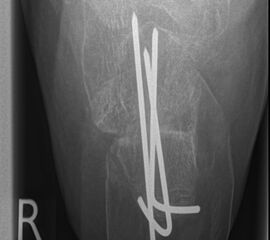

Liegt eine stark subduktische 5. Zehenposition vor, fräsen wir bevorzugt in der Kramertechnik für eine maximale Korrektur und Setzen für zwei bis drei Wochen einen intramedullären Draht nach proximal durch die Osteotomie (Abb. 27).

Abb. 27 a-d: Radiologische Darstellung intraoperativ (a) und vor dem Entfernen des Drahtes einer kompletten Schaftosteotomie mit intramedullärem Draht stabilisiert (b). Die Osteotomie wird minimalinvasiv durchgeführt und der Draht nach der Spülung über den gleichen Hautschnitt einfach in den Schaft hineingeschoben und die Osteotomie darüber stabilisiert. Das Köpfchen kann anschließend je nach Bedarf plantarisiert oder extendiert werden. Radiologische Verlaufskontrolle vor Entfernung des Drahtes (c-d).